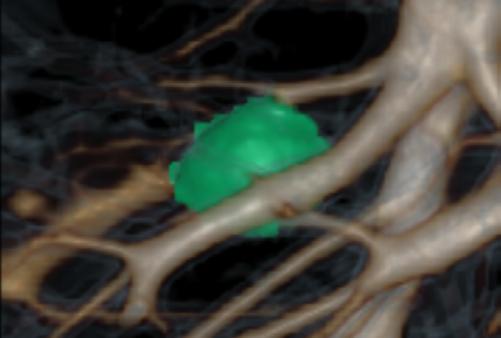

Femenino de 65 años, antecedente de hipertensión arterial de 20 años de evolución en control. Sin antecedentes familiares relevantes de enfermedades neurológicas. Acudió a consulta médica por deterioro progresivo en su capacidad motora y dificultades en las actividades diarias. Desde hace 2 años ha notado cambios en su marcha y en su habilidad para realizar movimientos finos con las manos principalmente del lado izquierdo, rigidez muscular, temblor en reposo siendo mayor del lado izquierdo y dificultad para iniciar y mantener el movimiento, especialmente al levantarse de una silla o al comenzar a caminar. Además, los familiares han observado que tiene una expresión facial inexpresiva y que su voz se ha vuelto más monótona. A la exploración física con expresión facial inexpresiva, temblor de reposo bilateral en manos de predominio izquierdo, rigidez muscular generalizada, más pronunciada en las extremidades superiores, bradicinesia evidente en la realización de movimientos finos de las manos, marcha festinante con pasos cortos y arrastrando los pies, reflejos osteotendinosos normales, no se observan déficits sensoriales. Se realiza adicionalmente la escala de Evaluación de la Enfermedad de Parkinson (UPDRS) con un total de 35 puntos, indicando moderada afectación de la enfermedad. Inicialmente se realiza una tomografía simple de cráneo, sin alteraciones estructurales, al no encontrar algún hallazgo se decide realizar posteriormente Resonancia Magnética Cerebral 1.5 Tesla: sin alteraciones estructurales significativas. Por este motivo y ante la alta sospecha clínica se realiza estudio de imagen molecular PET-RM con 6-[18F] FDOPA en equipo 3 Tesla en el cual se observa la disminución de la captación de la 6-[18F]FDOPA a nivel de putamen y caudado de predominio derecho evidenciando la degeneración dopaminérgica nigro presináptica a este nivel, con un patrón tipo 2 (Egg shaped) así como la mala definición de nigrosoma, estos hallazgos compatibles con enfermedad de parkinson. (Figura 1 y 2)

axial fusionada de PET-RM 3T con

con disminución de la captación del radiotrazador a nivel de ambos putámenes en la región posterior y media de predominio derecho así como disminución en el caudado ipsilateral.

2. Reconstrucción tridimensional avanzada de imagen híbrida PET-RM 3T con 6-[18F]FDOPA observando disminución de la captación del radiotrazador a nivel de ambos putámenes en la región posterior y media así como en el núcleo caudado derecho.

Figura 3. Reconstrucción mediante imagen molecular de imagen híbrida PET-RM 3T con 6-[18F] FDOPA observando disminución de la captación del radiotrazador a nivel de ambos putámenes en la región posterior, media y anterior así como en ambos núcleos ca dados de predominio derecho.

Figura 4. Reconstrucción mediante imagen molecular de imagen híbrida PET-RM 3T con 6-[18F]FDOPA observando captación adecuada y conservada del radiotrazador en el cuerpo estriado (ambos putámenes y núcleos caudados) en un paciente negativo para enfermedad de parkinson.